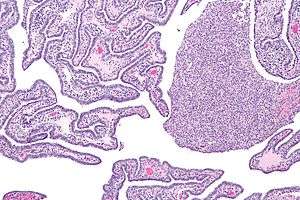

| Micrograph of acute and chronic salpingitis. H&E stain. | |

Acute and chronic salpingitis

There are two types of salpingitis: acute salpingitis and chronic salpingitis.